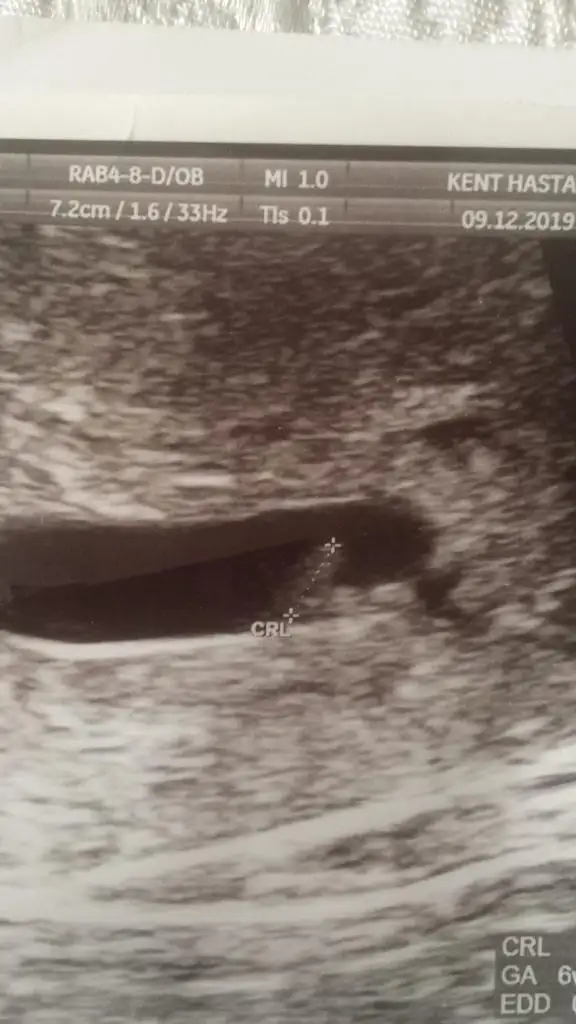

Bebek te mi görünüyor bana mı öyle geldiBu da benim minik davşanım5+0 da göründü tam

kesenin içi doluBu da benim minik davşanım5+0 da göründü tam

senin yolladıgın 6 haftalıkkendı herhalde demı canım

seninkininde içi doluuu5 haftalıktı 10 Aralık’ta 30 Aralık’ta gitcem cok merak ediyorum kalp atışını

6 haftalık ultrason goruntusune benzıyo